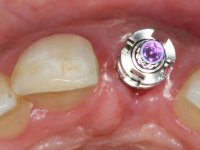

3) Colocação de um implante no espaço criado na zona do 21 associada a uma regeneração óssea guiada da zona,

Os cotos de óxido de zircónio são dos assuntos mais debatidos em implantologia. A sua resistência à fractura, as conexões externas e internas, a interacção entre o parafuso de retenção e o coto – todos estes assuntos são abordados repetidamente. No entanto, todos parecem concordar que os cotos de óxido de zircónio apresentam resultados altamente previsíveis, especialmente na restauração de dentes anteriores. Outro argumento em favor dos cotos de óxido de zircónio é a alta biocompatibilidade do material.

A comparação entre o óxido de zircónio e o dissilicato de lítio mostra que o último pode sofrer ataque ácido e ser silanizado e assim ser preparado para uma cimentação adesiva. Uma dica: no sentido de criar no coto de óxido de zircónio uma superfície susceptível de ser gravada pelo ácido, a superfície a ser colada pode ser recoberta com uma fina camada de cerâmica de adesão antes de modelar a coroa. Para este propósito, a ceram Zirliner é aplicada primeiro, depois aplica-se uma camada de ceram de dentina profunda na tonalidade desejada. Como resultado, a cor da dentina ilumina a restauração a partir do seu interior e cria a possibilidade de ser aplicado um protocolo de cimentação adesiva.